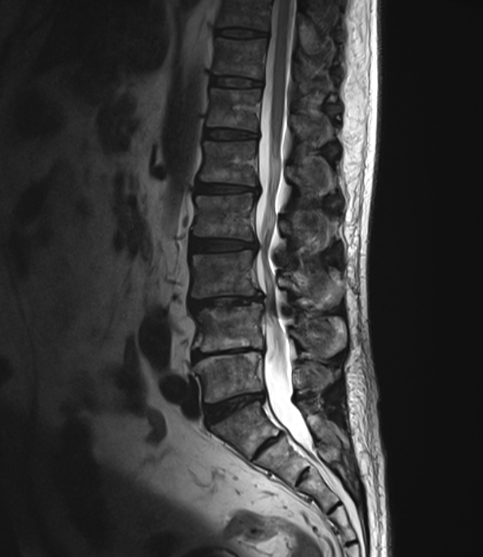

腰椎すべり症/ 脊柱管狭窄症

主訴 腰痛 左下肢痺れ

視診 左椎間板症状様疼痛回避姿勢

整形外科テスト SLRテスト 20°左(+++)

筋力検査 左長母趾伸筋低下

その他 輻輳反射 左低下

SLRテスト(−)

7週間後 15回目 左脛の痺れがやや残るも、9割の症状が改善